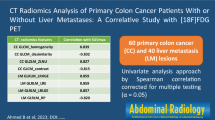

Abstract

Purpose

Standardized added metabolic activity (SAM) is a PET parameter for assessing the total metabolic load of malignant processes, avoiding partial volume effects and lesion segmentation. The potential role of this parameter in the assessment of response to chemotherapy and bevacizumab was tested in patients with metastatic colorectal cancer with potentially resectable liver metastases (mCRC).

Methods

18F-FDG PET/CT was performed in 18 mCRC patients with liver metastases before treatment and after five cycles of FOLFOX/FOLFIRI and bevacizumab. Of the 18 patients, 16 subsequently underwent resection of liver metastases. Baseline and follow-up SUVmax, and SAM as well as reduction in SUVmax (∆SUVmax) and SAM (∆SAM) of all liver metastases were correlated with morphological response, and progression-free and overall survival (PFS and OS).

Results

A significant reduction in metabolic activity of the liver metastases was seen after chemotherapy with a median ∆SUVmax of 25.3 % and ∆SAM of 94.5 % (p = 0.033 and 0.003). Median baseline SUVmax and SAM values were significantly different between morphological responders and nonresponders (3.8 vs. 7.2, p = 0.021; and 34 vs. 211, p = 0.002, respectively), but neither baseline PET parameters nor morphological response was correlated with PFS or OS. Follow-up SUVmax and SAM as well as ∆SAM were found to be prognostic factors. The median PFS and OS in the patient group with a high follow-up SUVmax were 10.4 months and 32 months, compared to a median PFS of 14.7 months and a median OS which had not been reached in the group with a low follow-up SUVmax (p = 0.01 and 0.003, respectively). The patient group with a high follow-up SAM and a low ∆SAM had a median PFS and OS of 9.4 months and 32 months, whereas the other group had a median PFS of 14.7 months and a median OS which had not been reached (p = 0.002 for both PFS and OS).

Conclusion

18F-FDG PET imaging is a useful tool to assess treatment response and predict clinical outcome in patients with mCRC who undergo chemotherapy before liver metastasectomy. Follow-up SUVmax, follow-up SAM and ∆SAM were found to be significant prognostic factors for PFS and OS.